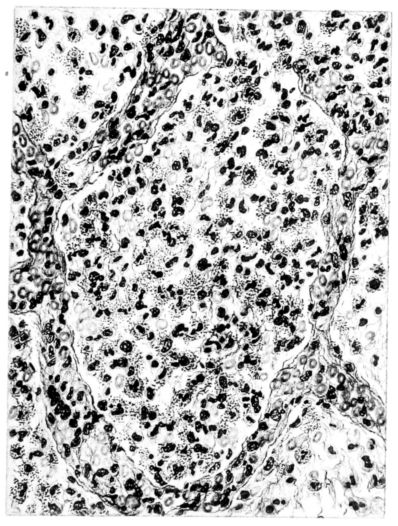

FIG. II. AUTOPSY NO. 98. DRAWING OF A SECTION THROUGH A TRACHEA SHOWING NECROTIZING HEMORRHAGIC INFLAMMATORY PROCESS OF THE MUCOSA.

The changes are less marked, perhaps, in the trachea than in its finer ramifications. The mucosa is constantly more or less destroyed and large areas, usually focal, are entirely devoid of their epithelial covering. This is replaced by a sparse exudate, composed largely of red blood cells, mucus, a small amount of fibrin, and nuclear fragments (Fig. II). It may dip into the submucosa for a short distance, but usually these indentures are associated with the ducts of the mucous glands into which the inflammatory reaction extends. A more striking feature than the exudate, however, is the edema and the congestion of the submucosa. The loose areolar tissue of the submucosa is spread widely apart, and throughout it distended blood vessels are very conspicuous. Occasionally such a vessel is broken and actual hemorrhage appears in the submucosa. Occasionally, too, the inflammation extends down the duct to the mucous gland itself, and here, also, aplastic inflammatory reaction is evident, inasmuch as the acini now stain intensely red with the cells undifferentiated from each other and specked here and there by broken remains of the dead nuclei (Fig. III). After the disease has continued for a short period, even at the end of five or six days, some regeneration of the epithelial lining may be seen (3) (Fig. IV). But despite this, the acute picture persists, and there goes on, side by side, an attempted repair characterized by epithelial regeneration and the same evidence of acute change. Since the lesion is essentially a superficial one, scars or contractures of any extent are not encountered in the trachea, even in examples of the disease that have ended fatally only after many weeks.[4]